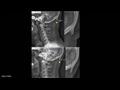

وبحسب ما نقلت صحيفة "ديلي ميل" البريطانية، فإن الشخص الذي يكثر من استخدام الهاتف الذكي، يظهر لديه ما يشبه شوكة عظمية في الجهة الخلفية من جمجمة الرأس، بسبب الانحناء والتركيز في شاشة الجهاز.

وتوضح الدراسة التي جرى إعدادها في جامعة "سان شان كوست" الأسترالية، أن جمجمة الإنسان أضحت تحدث هذه "الشوكة العظمية" بشكل متزايد.

وبوسع الكثيرين في الوقت الحالي أن يتحسسوا هذه الشوكة في مؤخرة الرأس، أما الأشخاص الصلع فيمكن رصدها بسهولة في رؤوسهم.

وتبرز هذه الشوكة العظمية بشكل أسرع لدى الشباب الذين تتراوح أعمارهم بين 18 و30 سنة، واعتمدت الدراسة على عينة من ألف جمجمة.